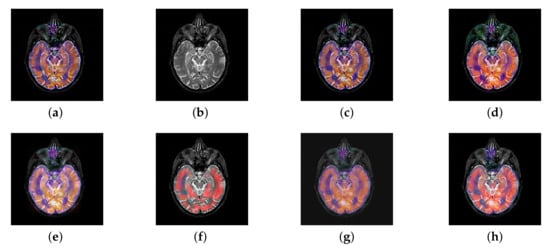

In this section, there are four image sets to fuse, each containing a MRI image and its corresponding CBF image in Figure 41. In Figure 42, Figure 43, Figure 44 and Figure 45, it can be seen that the structural information of fusion images obtained by our algorithm is complete. The color is not distorted, and the spectral features are natural. The fusion image based on DTCWT and NSCT algorithm have high color fidelity but less structural information. Other algorithms, such as IGM, LPSR, and FusionCNN, only focus on the structural information of the MRI image and ignore the color information of the fused image. Although the image structure information obtained by DDcGAN fusion algorithm is relatively complete, the edge of color information is not clear, which has a great influence on image contrast.

Figure 42.

Fused medical images obtained by different algorithms (Figure 41a,b): (a) DTCWT, (b) GFF, (c) NSCT, (d) LPSR, (e) IGM, (f) FusionCNN, (g) DDcGAN, and (h) FusionNet.

Figure 43.

Fused medical images obtained by different algorithms (Figure 41c,d): (a) DTCWT, (b) GFF, (c) NSCT, (d) LPSR, (e) IGM, (f) FusionCNN, (g) DDcGAN, and (h) FusionNet.

Figure 44.

Fused medical images obtained by different algorithms (Figure 41e,f): (a) DTCWT, (b) GFF, (c) NSCT, (d) LPSR, (e) IGM, (f) FusionCNN, (g) DDcGAN, and (h) FusionNet.

Figure 45.

Fused medical images obtained by different algorithms (Figure 41g,h): (a) DTCWT, (b) GFF, (c) NSCT, (d) LPSR, (e) IGM, (f) FusionCNN, (g) DDcGAN, and (h) FusionNet.